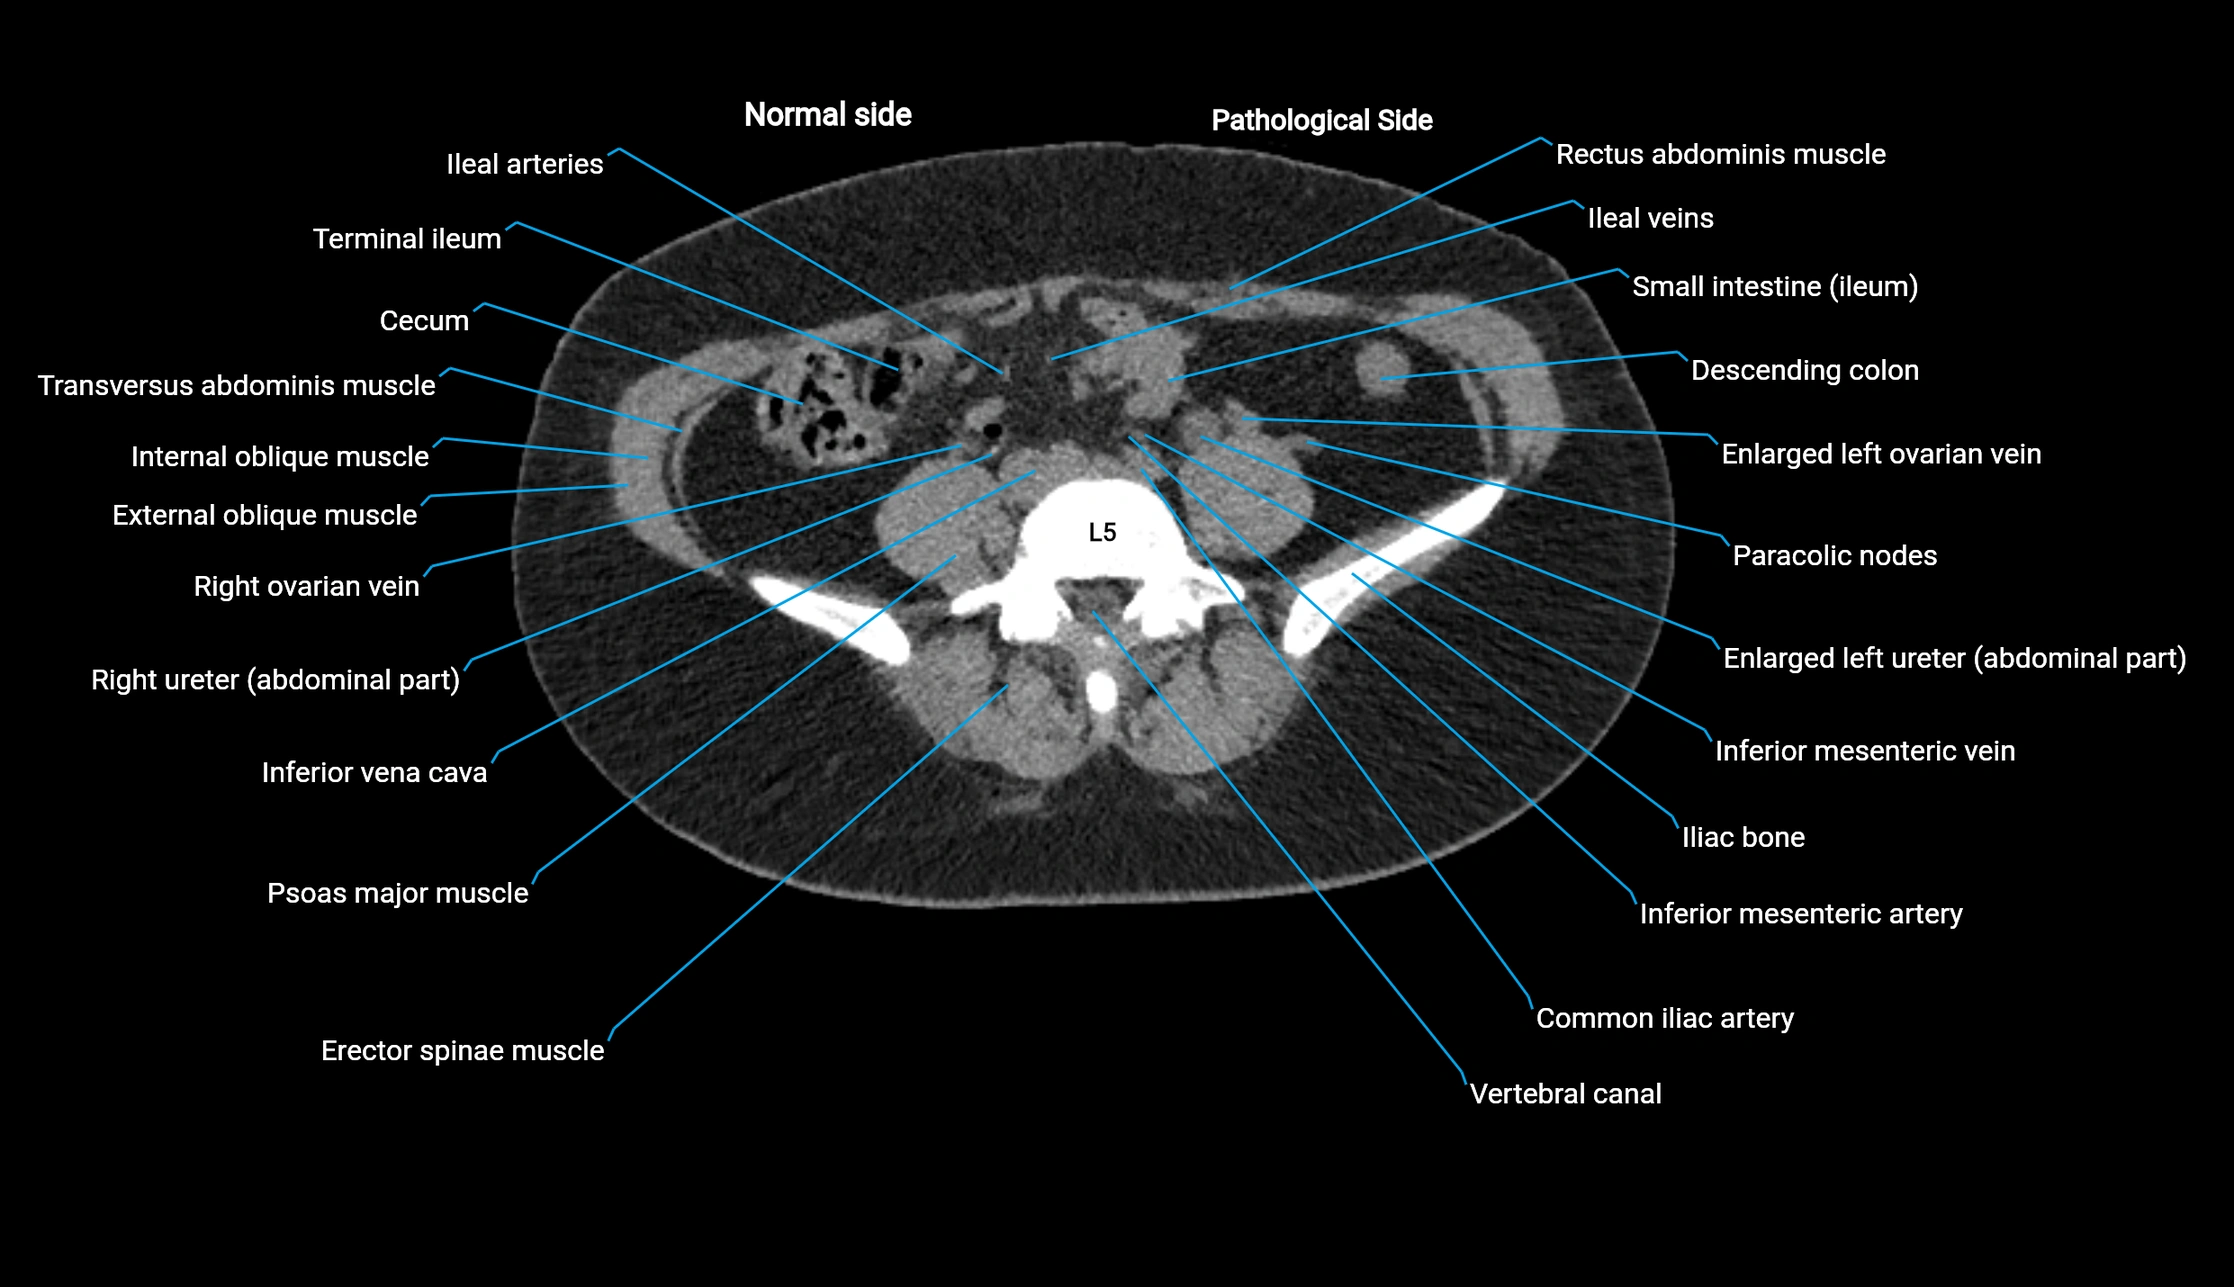

CT image

image